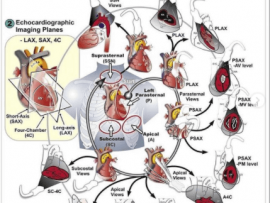

Lee masParasternal short axis view, Apical four chamber view “A4C”. By placing the probe in the 5th to 7th intercostal space with a pointer directed to the lateral side till u..